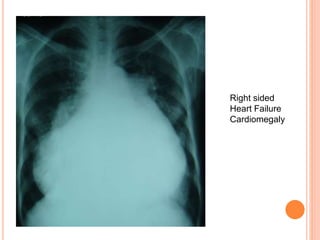

Right sided

Heart Failure

Cardiomegaly

 Chest X-ray

-cardiomegaly

-pulmonary edema